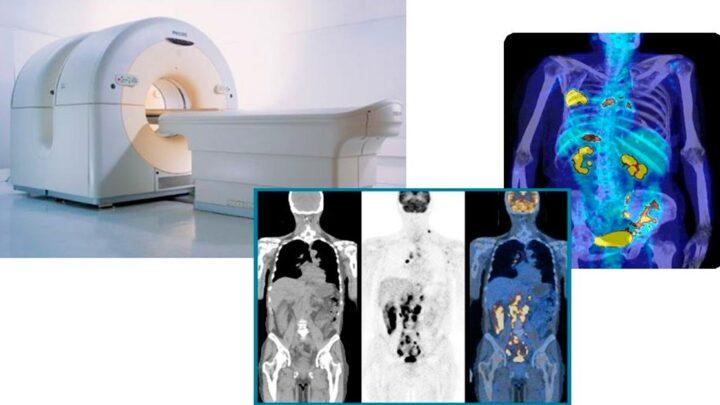

O que é Tomografia Computadorizada Vamos falar hoje sobre tomografia computadorizada. Esse exame cujo atividade é semelhante ao raio X…

A tomografia por emissão de pósitrons, ou PET, é um procedimento popular realizado no Departamento de Medicina Nuclear. A radiação para…